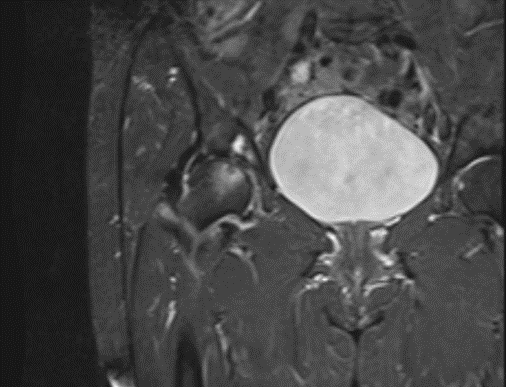

Sau khi chụp MRI kết quả cho thấy tổn thương vùng chỏm xương đùi phải với vùng giảm tín hiệu trên T1,T2, tăng tín hiệu trên STIR, những tổn thương sớm này không thể quan sát thấy được trên chụp Xquang thường quy.

Hình ảnh Xquang và MRI của bệnh nhân

Bệnh nhân được chẩn đoán hoại tử chỏm xương đùi phải giai đoạn II theo phân loại Arlet – Ficat. Với những tổn thương phát hiện sớm như thế này, bệnh nhân sẽ được điều trị nội khoa nhằm bảo tồn khớp háng.